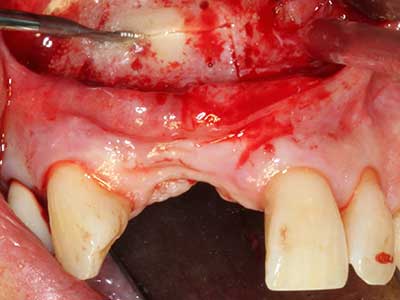

Abb. 8: Nach erfolgtem Sinuslift wird der krestale Knochensplint auf dem defizitären Kieferkamm fixiert.

Abb. 9. Unterfütterung mit bovinem Knochenersatzmaterial (Cerabone 0,5-1mm, Botiss Biomaterials, Berlin) und Eigenknochen (palatinale Ansicht).

Abb. 10: Abdeckung des augmentierten Bereiches mit einer langzeitstabilen Perikardmembran (Jason Kollagenmembran, Botiss).